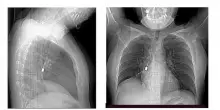

Scoprono un cacciavite odontoiatrico incastrato nel bronco: la donna aveva tosse e dolore al petto

Un cacciavite odontoiatrico inalato accidentalmente e rimasto incastrato in un bronco polmonare. È la scoperta choc che ha portato una giovane donna al Pronto Soccorso dopo giorni di tosse...